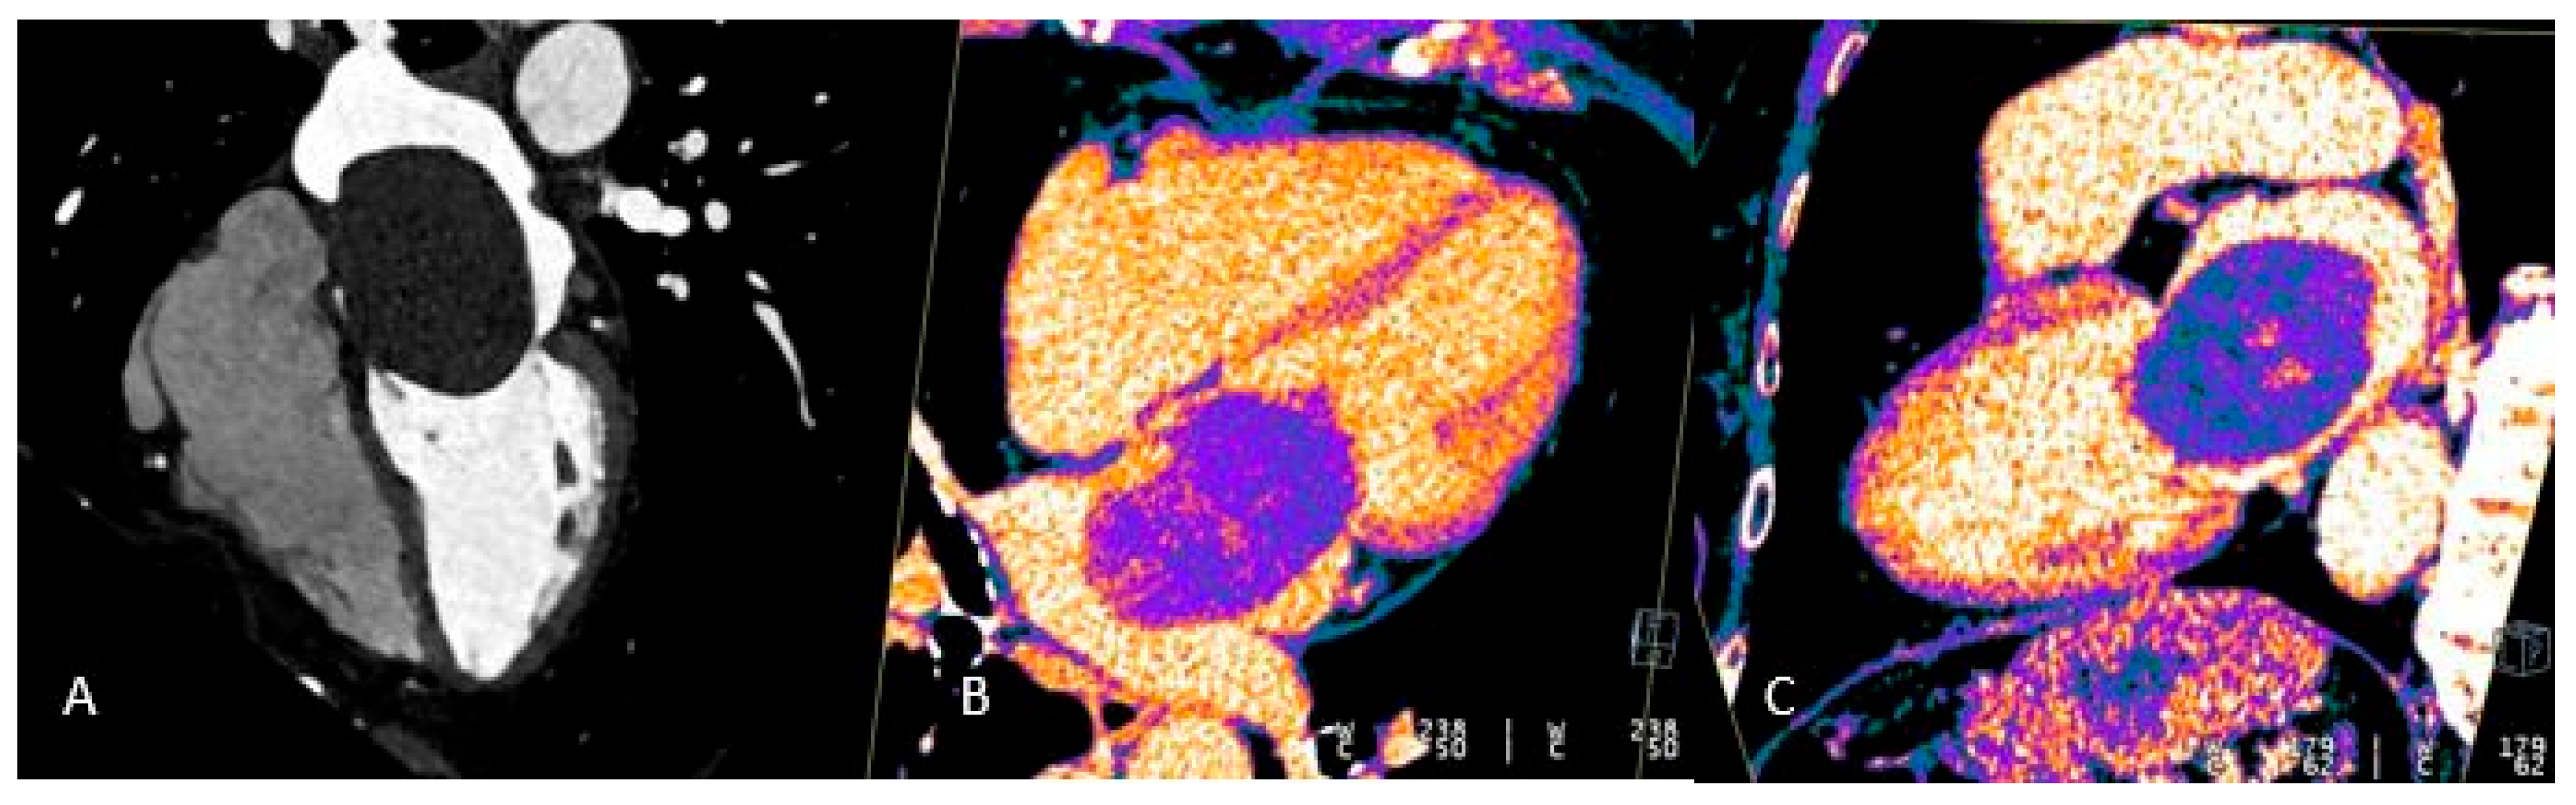

1.1.4. Dual Energy Acquisition and Late Enhancement Scans

New-generation CT systems leverage Dual Energy acquisition for detailed tissue characterization, allowing the creation of virtual non-contrast datasets and the detection of myocardial fibrosis—an indicator of ischemia, myocarditis or cardiomyopathy. They also support late-enhancement imaging: after the initial contrast bolus, a second injection is given and, following an eight-minute delay, new scans are acquired so that fibrotic myocardium—having a higher affinity for the contrast agent—stands out against normal myocardial tissue (Figure 1) [20,21].

Figure 1. Long-axis multiplanar reconstruction of the left ventricle acquired from a late iodine enhancement phase (8 minutes after dual-bolus injection) in a patient with hypokinesia of the inferior apical wall of the left ventricle. A) Virtual monoenergetic image 140 High-Kev. B) Virtual monoenergetic image 40 Low-Kev. C) Iodine Map image. A subendocardial iodine distribution (post ischemic scar) can be detected only using high tissue contrast low-Kev image and iodine map distribution recon.